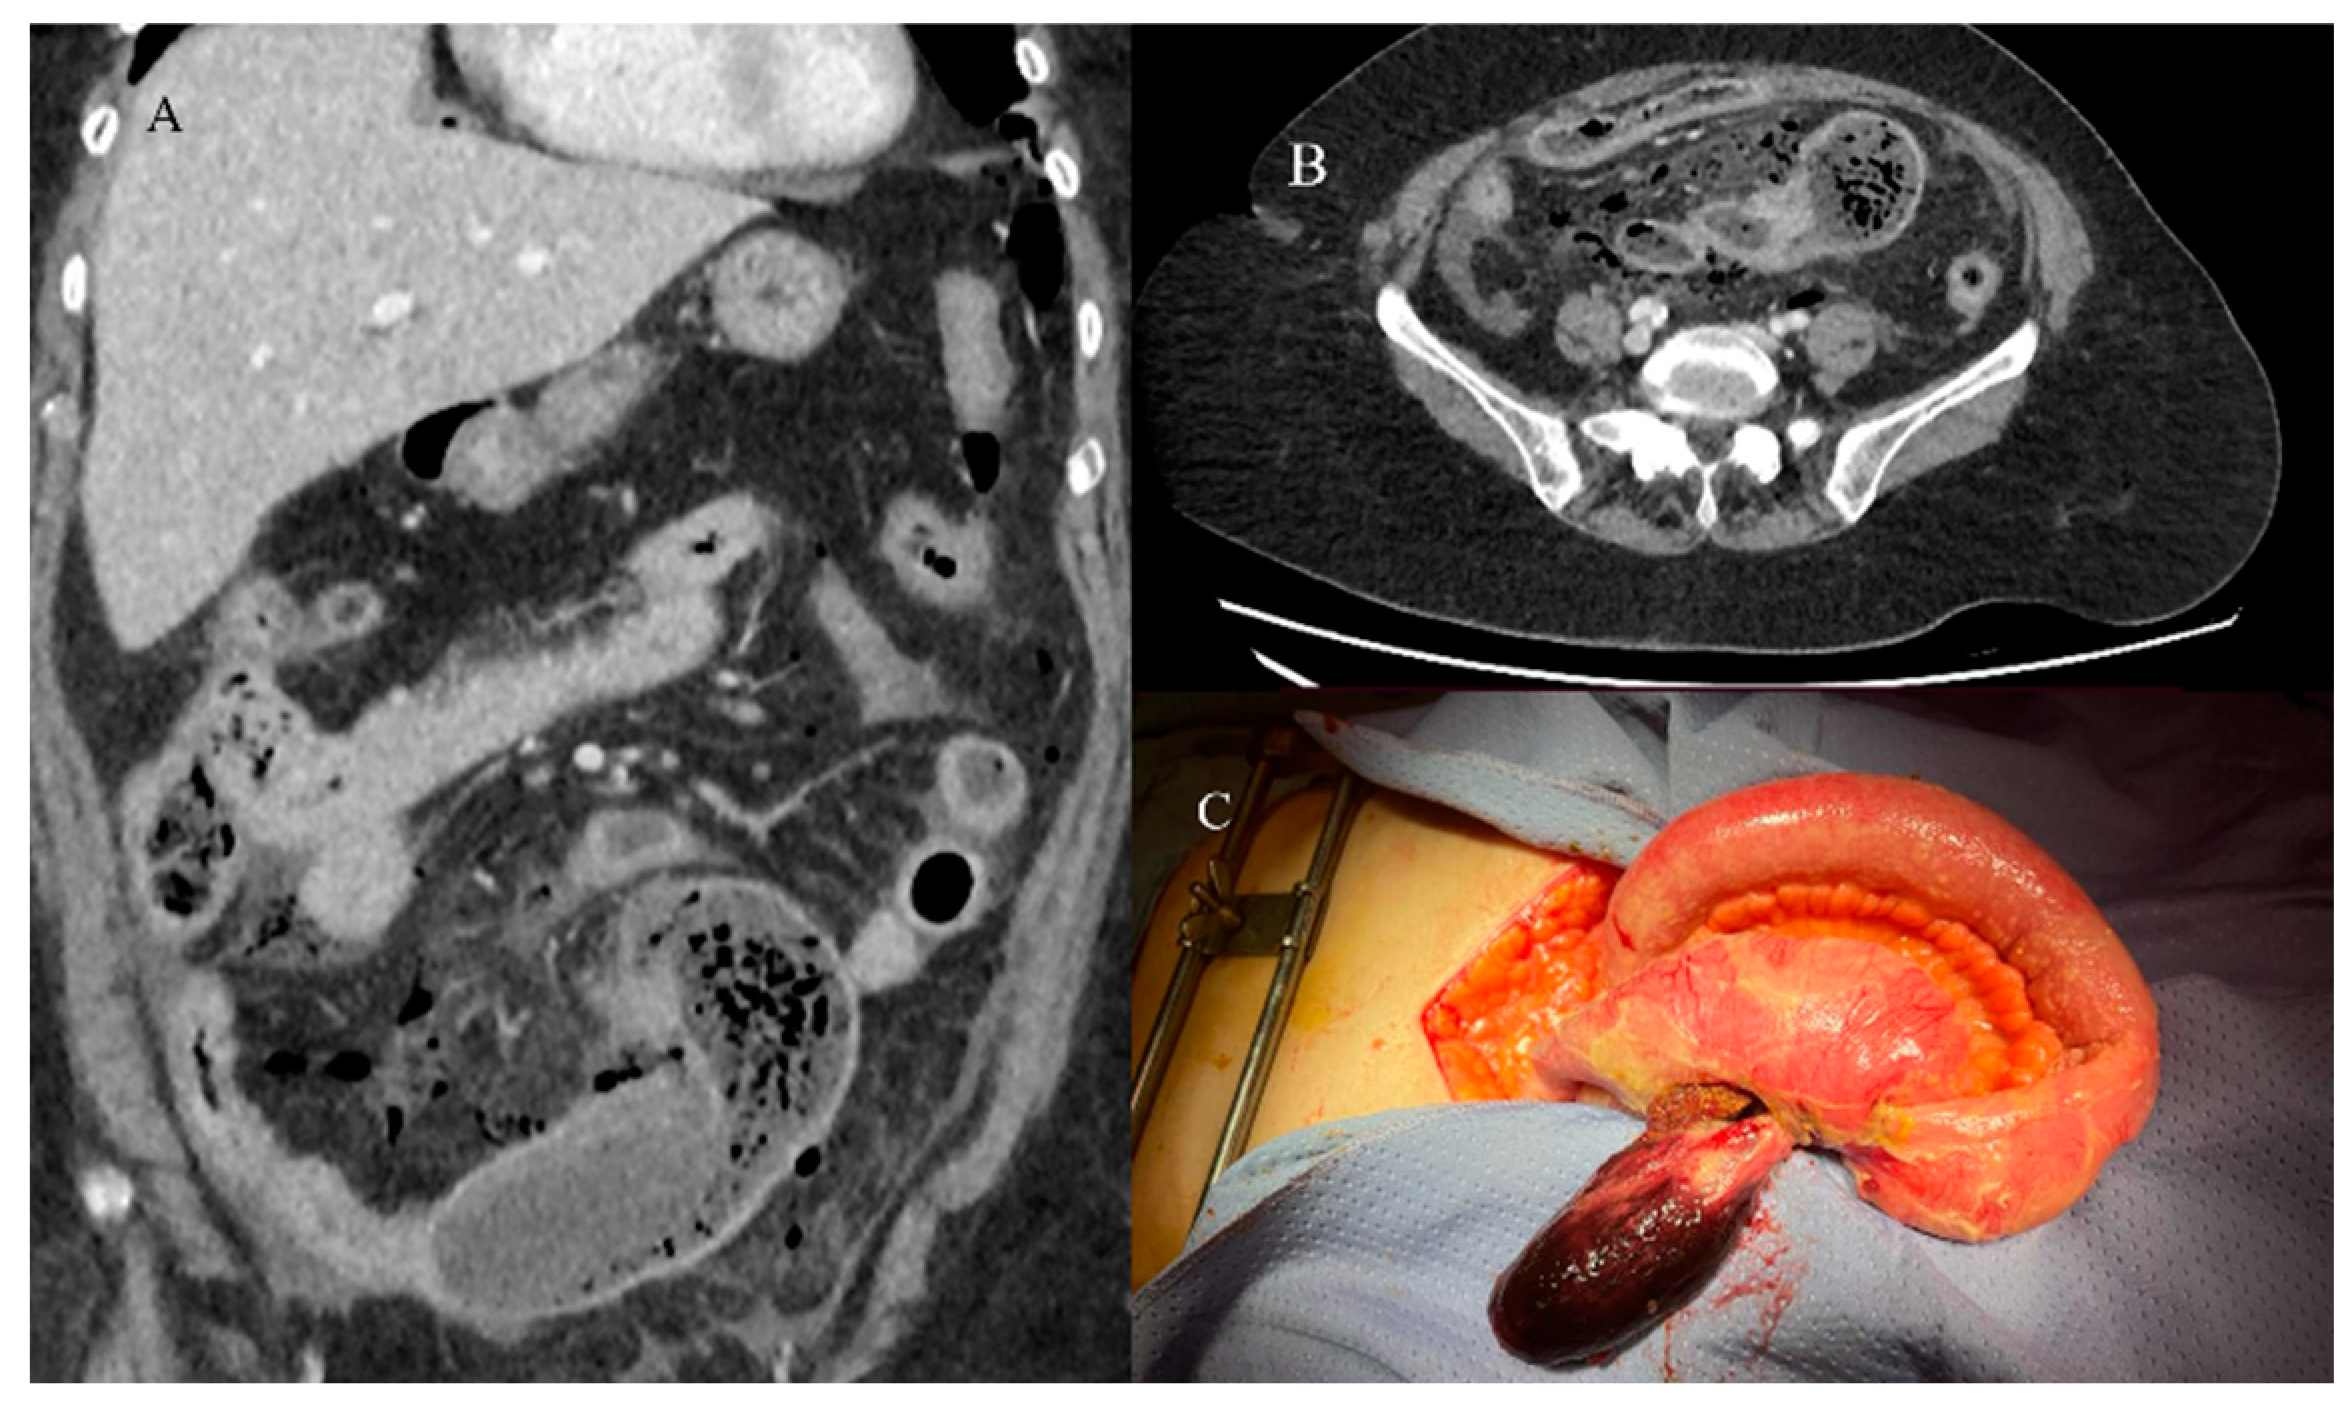

- Chao, T.C.; Chao, H.H.; Jan, Y.Y.; Chen, M.F. Perforation through small bowel malignant tumors. J. Gastrointest. Surg. 2005, 9, 430–435. [Google Scholar] [CrossRef] [PubMed]

- Mooghal, M.; Ahmad, A.; Safi, A.; Khan, W.; Ahmad, N. Impending perforation near ileocecal junction due to phytobezoar impaction and intraluminal polyp: A case report. J. Med. Case Rep. 2022, 16, 124. [Google Scholar] [CrossRef] [PubMed]

- Carney, B.W.; Khatri, G.; Shenoy-Bhangle, A.S. The role of imaging in gastrointestinal bleed. Cardiovasc. Diagn. Ther. 2019, 9 (Suppl. S1), S88. [Google Scholar] [CrossRef]

- Pouli, S.; Kozana, A.; Papakitsou, I.; Daskalogiannaki, M.; Raissaki, M. Gastrointestinal perforation: Clinical and MDCT clues for identification of aetiology. Insights Imaging 2020, 11, 31. [Google Scholar] [CrossRef]